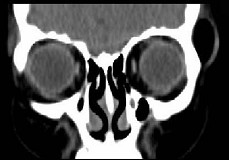

女,31岁,在左眶外上缘发现一包块,质软,余所见无明显异常。如图所示病灶应诊断为 ( ) 2YJB-16841.jpg 2YJB-16842.jpg 2YJB-16843.jpg 2YJB-16844.jpg

题型: 单选题 分类: 眼科学

• A.畸胎瘤

• B.错构瘤

• C.脂肪瘤

• D.表皮样囊肿

• E.淋巴管瘤